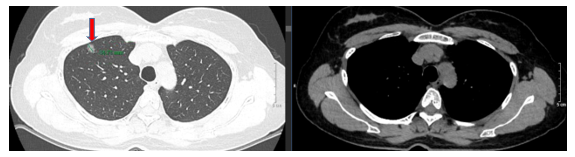

-    Chụp cắt lớp vi tính lồng ngực (trước mổ), kết quả cho thấy: Nhu mô thùy trên phổi phải có nốt bán đặc bờ không đều đường kính 10mm (có tính chất ác tính), nốt kính mờ đường kính 7mm. Không thấy hạch to hay khối choán chỗ trong trung thất.

Hình 1: Hình ảnh cắt lớp vi tính lồng ngực trước mổ có nhu mô thùy trên phổi phải có nốt bán đặc bờ không đều đường kính 10mm (mũi tên đỏ)